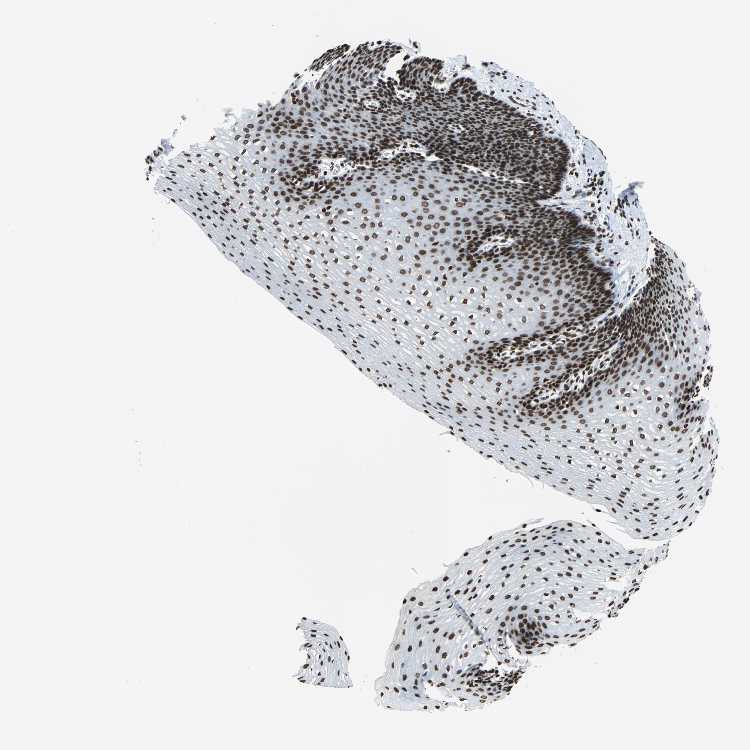

ESOPHAGUS - Antibody stainingi

Antibody staining in the annotated cell types in the current human tissue is reported as not detected, low, medium, or high, based on conventional immunohistochemistry profiling in selected tissues. This score is based on the combination of the staining intensity and fraction of stained cells.

Each image is clickable and will lead to virtual microscopy that enables deeper exploration of all samples and also displays staining intensity scores, fraction scores and subcellular localization as well as patient and tissue information for each sample.

Antibody HPA042205Antibody HPA043013Antibody HPA048671Antibody CAB007814

Squamous epithelial cells HighHighMediumHigh